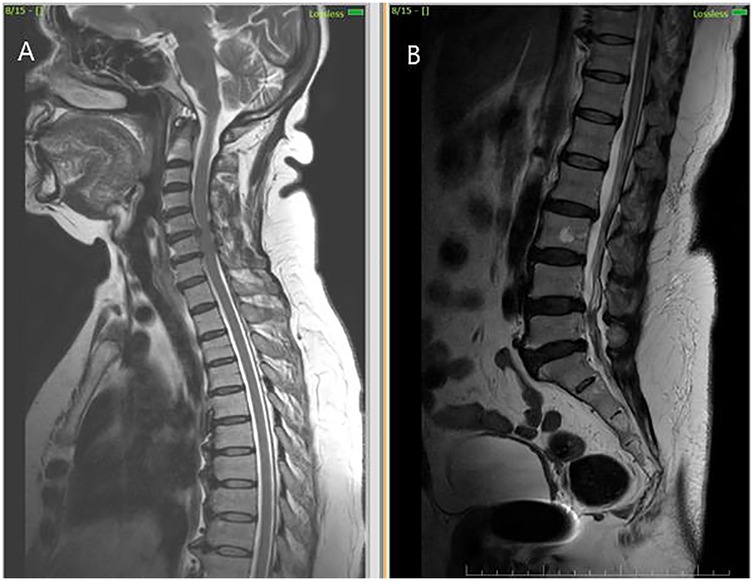

Figure 3

MRI scans showing two views of the spine. Image A depicts the cervical spine in a sagittal view, detailing vertebrae and spinal cord. Image B shows the lumbar spine in a sagittal view, highlighting lumbar vertebrae and intervertebral discs.

Figure 3. MRI cervical and lumbar spine findings suggestive of spondylosis. (A) Sagittal T2-weighted MRI shows cervical spondylosis with disc degenerative changes (B) Sagittal T2-weighted MRI shows lumbar spondylosis with disc degenerative changes.

Initial investigations (CBC, ESR, CRP, renal and liver function, echocardiography, ECG) were unremarkable. MRI thoracolumbar spine was performed 1 month and 28 days after symptom onset. MRI brain showed no signs of infarction or demyelination. MRI thoracolumbar spine demonstrated T2 and STIR hyperintensity involving the anterior horn and intermediate zone of the left hemicord at D12-L1, without contrast enhancement or mass effect. There was no evidence of cord compression, hematoma, or abscess (Figures 2A–D). MRI of the cervical and lumbar spine showed spondylotic changes with no significant cord involvement (Figures 3A,B). Poor-quality DWI was obtained, limiting diagnostic utility (acknowledged as a limitation). No follow-up MRI was performed.

The temporal relationship of infarct onset immediately after spinal anaesthesia further distinguishes this case. While neuraxial anaesthesia is generally considered safe, rare complications such as spinal cord ischaemia have been reported, usually secondary to hypotension, vasospasm, or mechanical injury (25). In this case, there were no haemodynamic fluctuations, technical difficulties, or radiologic evidence of hematoma or compressive pathology. Nevertheless, the close procedural timing raises the possibility of anaesthesia-induced microvascular compromise, particularly affecting a sulcal artery. This mechanism, although speculative, remains plausible given the vascular fragility in elderly patients and the confined vascular supply of the anterior spinal system. This case reinforces the importance of considering vascular causes in acute myelopathy, especially when imaging localises a unilateral anterior lesion. Potential risk factors include advanced age, pre-existing cervical and lumbar spondylosis, vascular fragility or subclinical atherosclerosis.